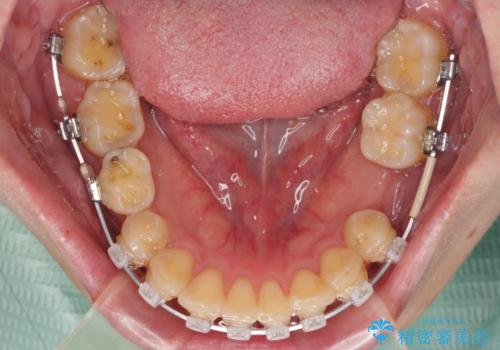

- 矯正装置

- クリアブラケット

- 治療期間

- 2年4ヶ月

- 治療回数

- 30回以上